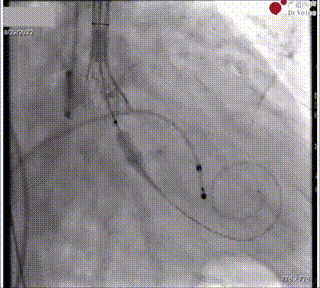

图8. 术中食道超声证实瓣架处于0位

图9. 瓣膜稳定脱钩,瓣膜初始形态

即刻食道超声见瓣架展开充分,微量瓣周漏,平均跨瓣压差7mmHg。